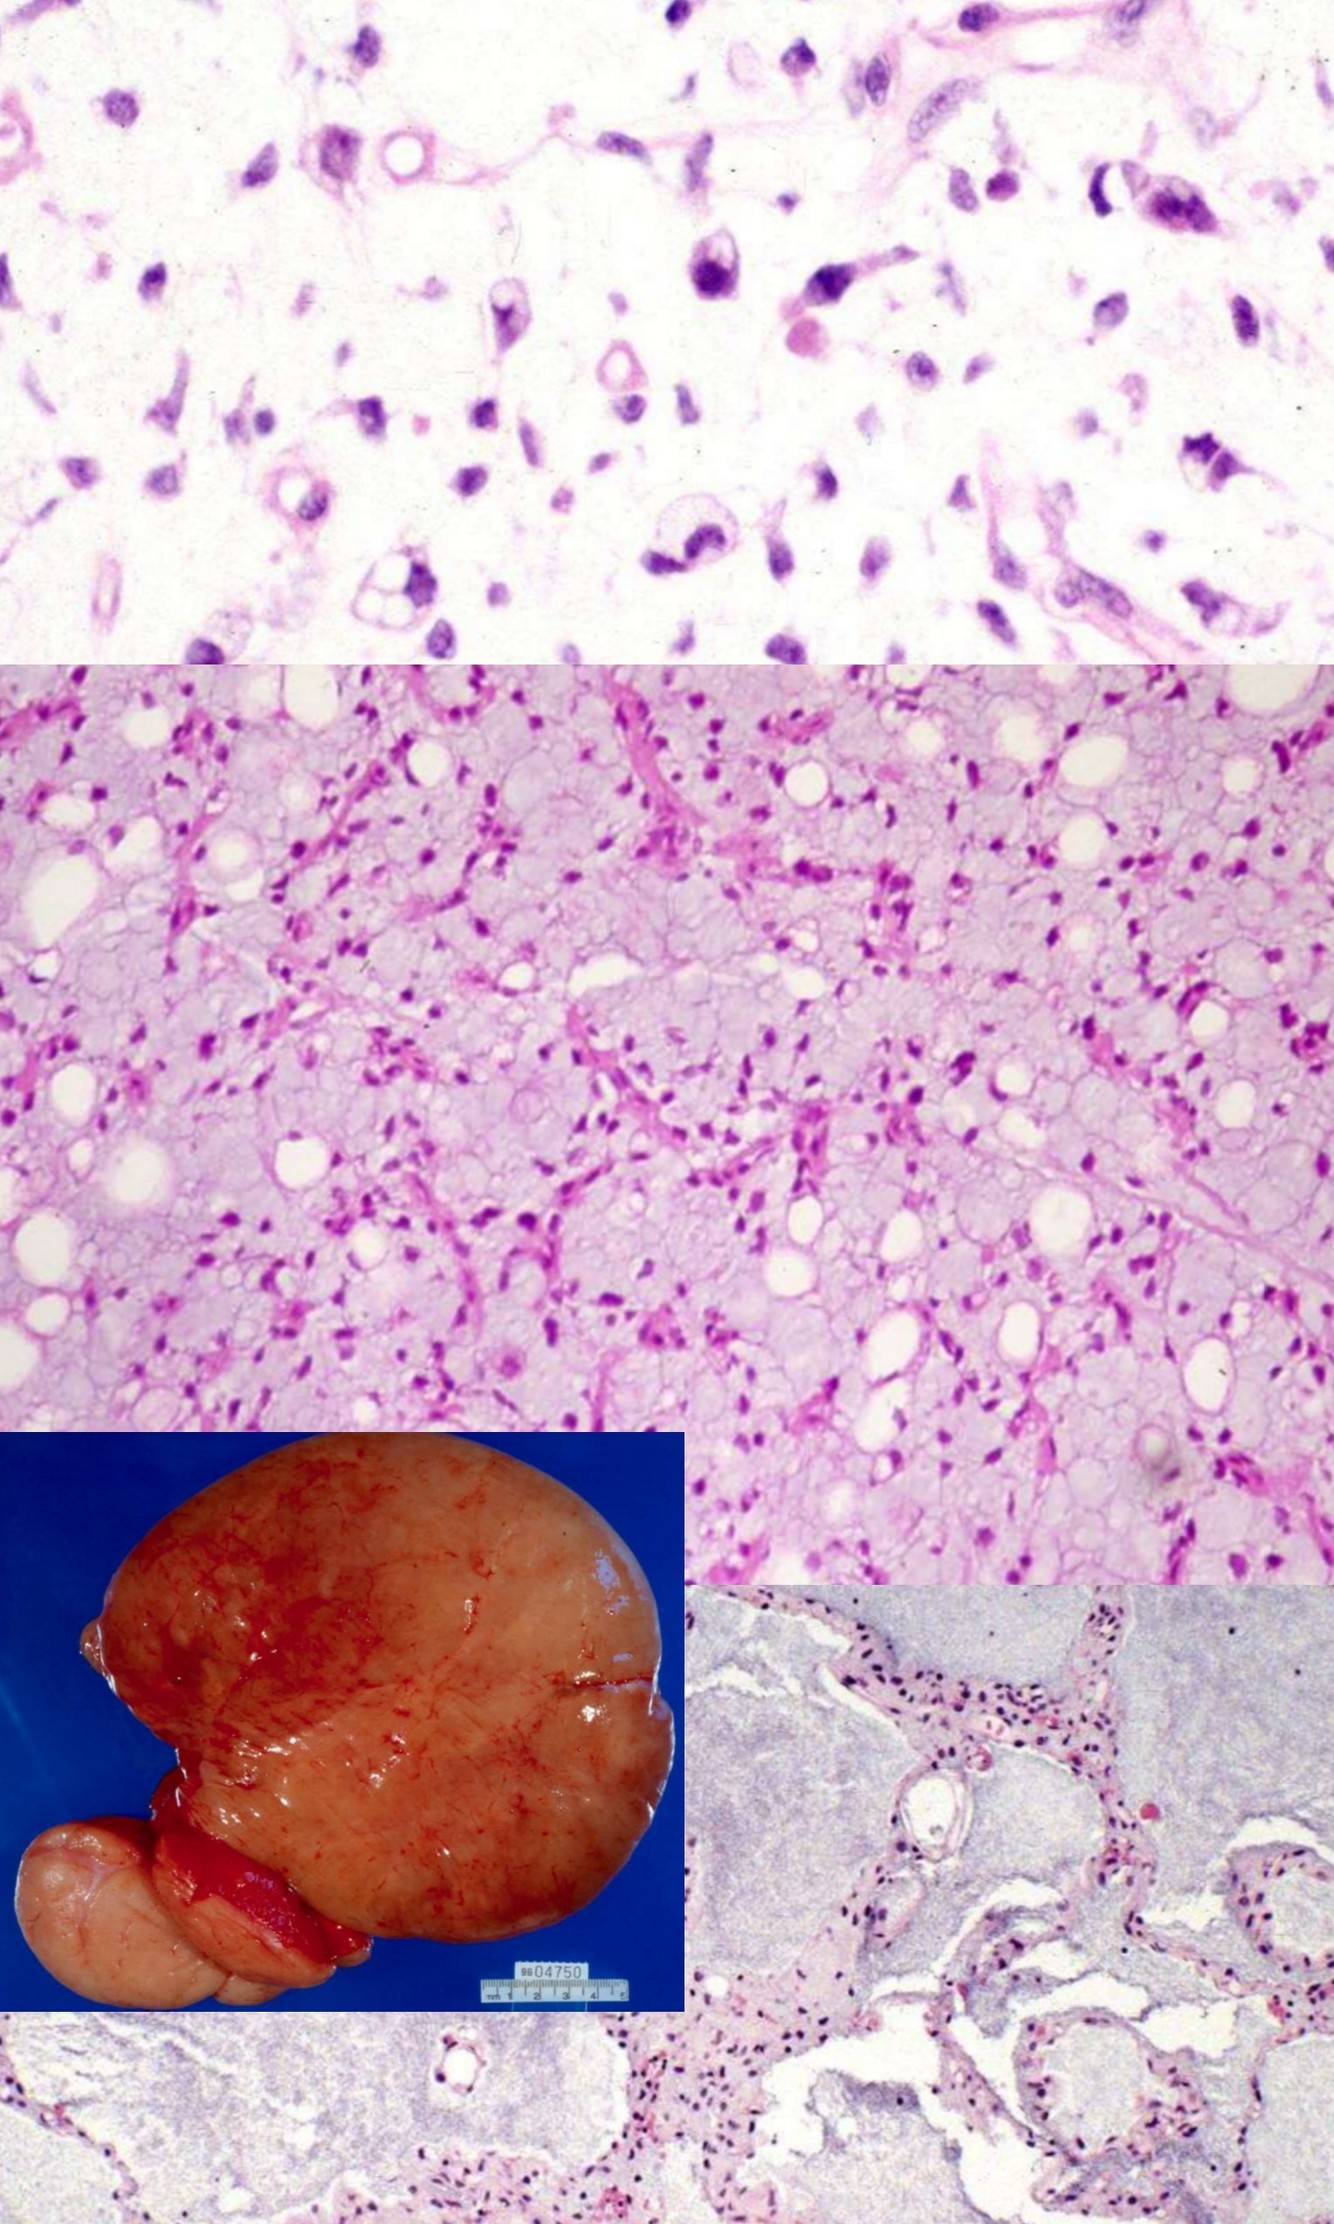

MYXOID LIPOSARCOMA/ROUND CELL

• t(12;16) translocation

• Histologic triad: abundant stromal mucin, delicate plexiform vasculature, lipoblastic differentiation

• Myxoid and round cell liposarcomas represent opposite ends of spectrum

LIPOBLASTOMA

• Genetics:

• Rearrangement of 8q11 approximately q13 region in 82%, includes PLAG1 gene

• Produces HAS2-PLAG1 and COL1A2-PLAG1 hybrid genes

• Also polysomy chromosome 8

• t(3;8)(p13;q21.1) also described

• Infants and young, M > F

• Extremities > trunk, head and neck

• Painless superficial soft tissue mass, 75% on left side

• Histology:

• Almost always subcutaneous

• Multilobular growth pattern

• Admixture of immature cells, stromal mucin and plexiform vessels

EXTRASKELETAL MYXOID CHONDROSARCOMA

• Deep soft tissues of extremities

• t(9;22) translocation

• Multinodular growth pattern, abundant stromal mucin

• Linear cords of eosinophilic cells, sometimes rhabdoid in appearance

• Variably S100+, keratin -, EMA -

ALVEOLAR SOFT PART SARCOMA

• t(X;17)

• Chromosomen1, 5, 13, 17 abnormalitys

• Clinical:

• Deep soft tissue of oral cavity, pharynx, mediastinum, thigh/leg

• Usually young females

• Highly malignant, although clinical course is slow/indolent

• Metastases up to 30 years later to veins, lungs, other

• Lung metastases may be presenting feature

• Gross:

• Well circumscribed, large, gray-yellow, hemorrhage, necrosis

• 2-14 cm

• Well defined nests of cells separated by fibrous stroma

• Alveolar pattern if cells discohesive

• Composed of large polygonal cells with granular eosinophilic cytoplasm, vesicular nuclei, prominent nucleoli

• Vascular invasion common; also characteristic rod-shaped crystalloids

• No/rare mitotic figures, minimal pleomorphism

• Positive: TFE3, PAS+ diastase resistant needle-like structures, MyoD1 (cytoplasmic only)

• Prognostic impact:

• Size, presence of 17q25 abnormality, AJCC stage, age

• Diff DX: metastatic renal cell ca, paraganglioma